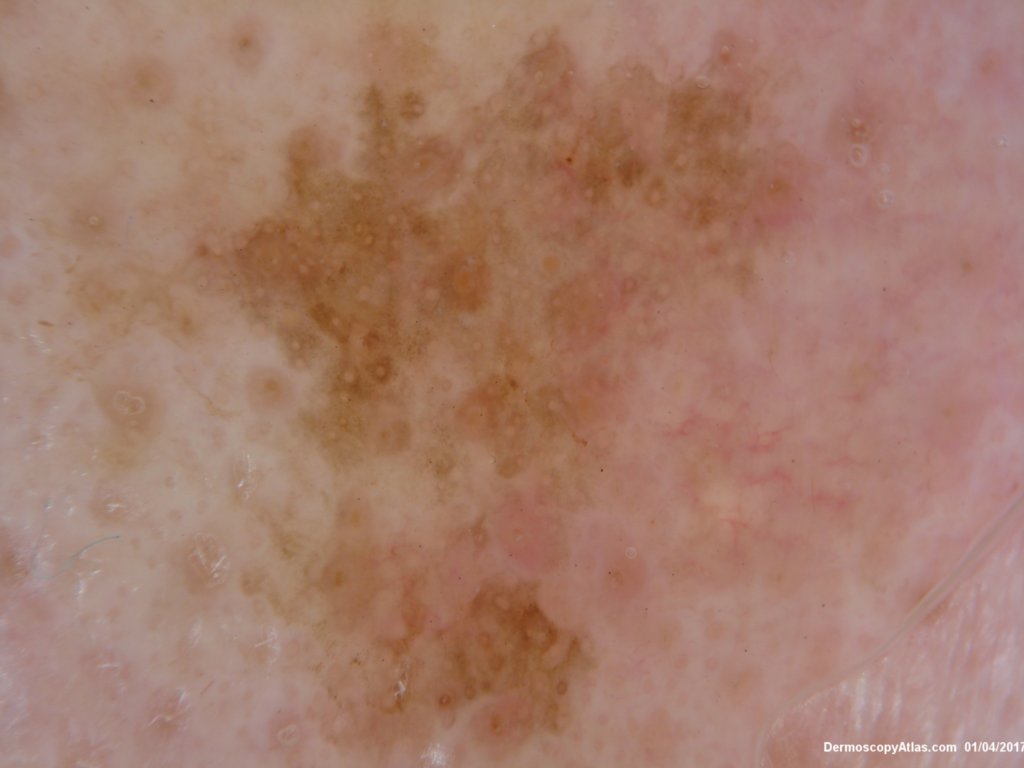

Site: Nose

Diagnosis: Lentigo Maligna

This lesion had slowly grown over 6 months. No PH of non melanoma skin cancers or melanoma .

The Dermatoscopy shows partial grey circles and the histology shows a lentiginous proliferation of atypical melanocytes involving the hair follicles.

Reported as lentigo maligna. Excised with a graft.